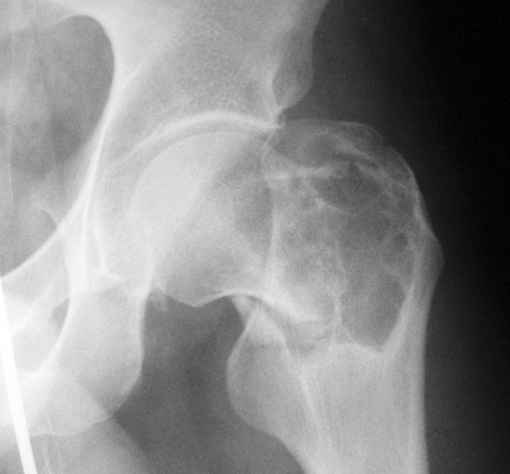

Уважаемые коллеги! Больной (1974 г.р.) травма 26.01.2009г., у пал на ра-боте с высоты своего роста, доставлен в одну из горбольниц Екатеринбурга в травматологическое отделение. На рентгенограмме выявлен патологический перелом чрезвертельной области левого бедра.

Доброкачественная опухоль (ОБК?, энхондрома?), по данным RS. Дополнительно произведено КТ. Наложено скелетное вытяжение.

Прилагаются: рентгенограмма и данные СТ